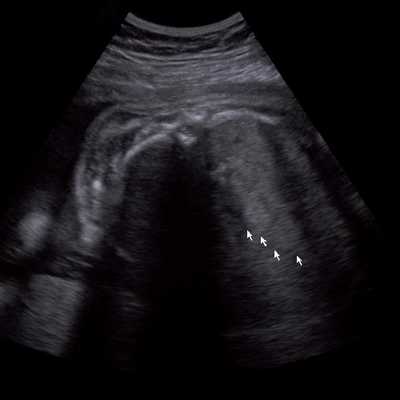

Под диафрагмой справа визуализировалось гиперэхогенное опухолевидное образование несколько неоднородной солидной структуры, с четкими ровными контурами, размером 50x38x35 мм. К нижнему полюсу данного образования прилежала правая почка, имеющая нормальные размеры, форму и структуру. Нижняя полая вена была смещена кпереди и влево. Обращала на себя внимание выраженная гепатомегалия, причем структура печени не была однородной. Она содержала множественные гиперэхогенные включения размерами до 17 мм, окруженные тонким гипоэхогенным периферическим ободком. Цветовое допплеровское картирование(ЦДК) демонстрировало интенсивную периферическую васкуляризацию опухоли (рис. 1-3).

Рис. 3. Метастазы в печени плода. Поперечное сечение брюшной полости плода. Гепатомегалия. В структуре печени плода определяются округлые включения несколько повышенной эхогенности (стрелки), с гипоэхогенным ободком - метастазы.

В представленном наблюдении картина нейробластомы надпочечника была не совсем классической. То, что это супраренальное образование - очевидно, так как оно прилежало к почке, имеющей нормальную форму, размеры и структуру. Опухоль имела капсулу, однородную гиперэхогенную структуру, что не характерно для нейробластомы надпочечника. Поэтому дифференциальную диагностику проводили с кровоизлиянием в надпочечники, опухолью Вильмса, экстралобарным легочным секвестром, ретроперитонеальной тератомой.